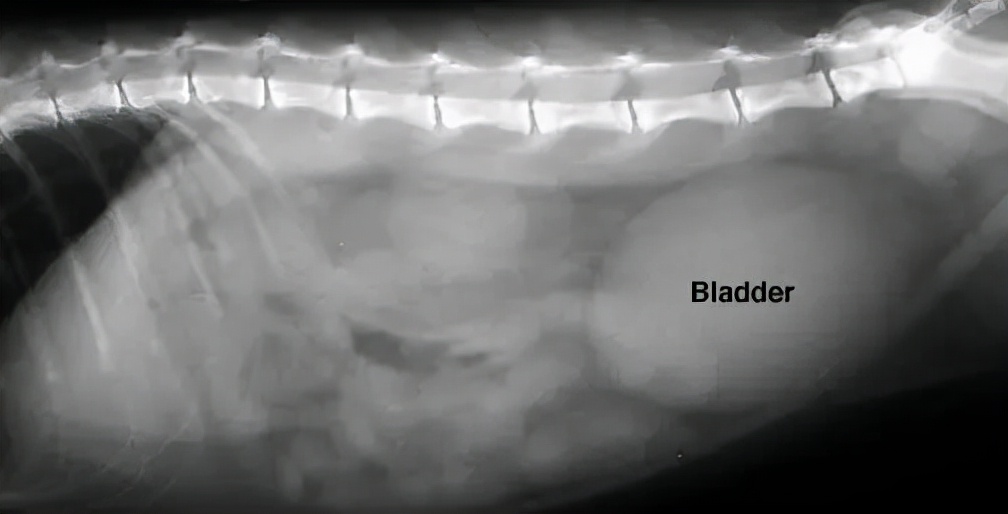

↑图片右侧的的椭圆形影像是一个充盈的膀胱

对于小猫咪来说,最重要的是尽快恢复尿道通畅。